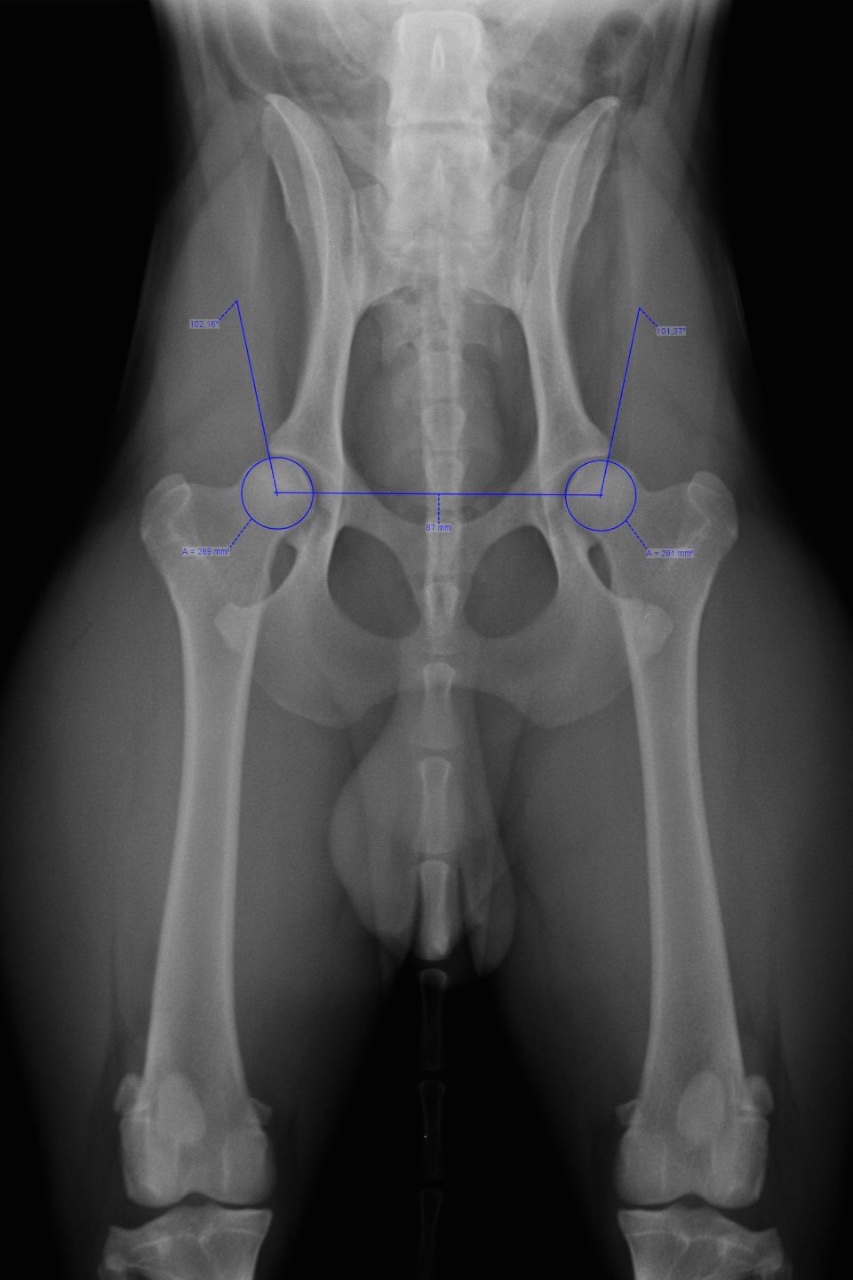

Durch die Möglichkeiten digitaler Bildbearbeitung und diverser Software können wir genaue Messungen durchführen. z.B.: exakte HD-Messung, oder objektive Herzgrößenmessungen.

Wegen der Qualität unserer Bilder und dem hohen Maß an Unbefangenheit in der Befundung, sind wir seit dem Jahr 2000 Vertrauenstierarzt-praxis, sowie offizielle HD, ED/OCD - Röntgenstelle des SVÖ und ÖKV.